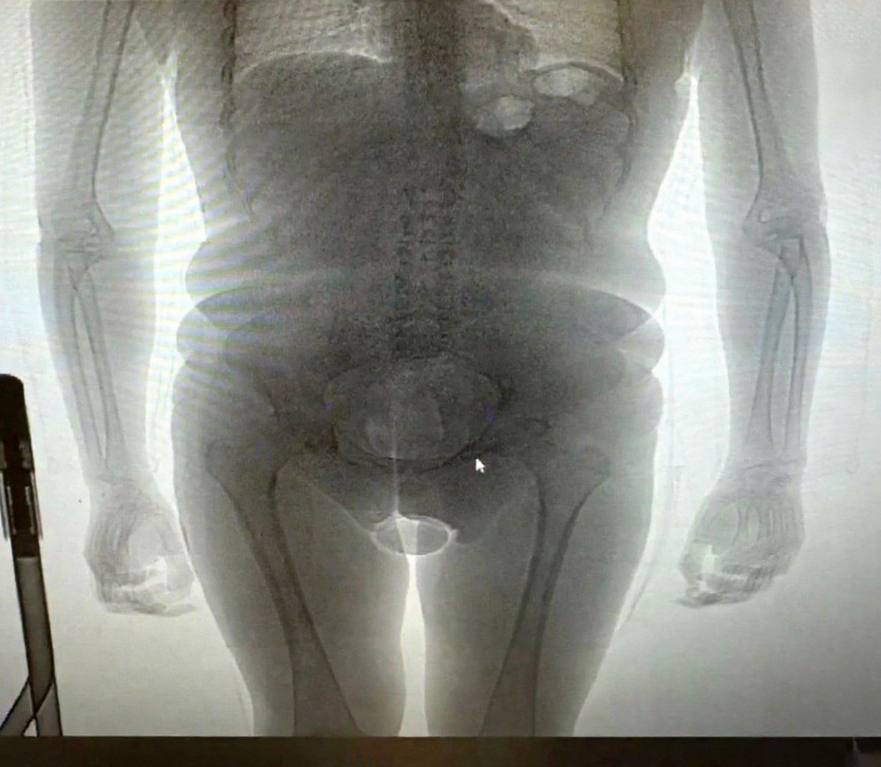

Изъято 2 презерватива, в которых находилось около 250 граммов кокаина. В отношении задержанного возбуждено уголовное дело по статье о незаконном перемещении наркотических средств через государственную границу. Продолжается следствие для выявления каналов поставки и возможных соучастников преступления. Подобные операции подчеркивают высокую эффективность работы российских таможенных служб в борьбе с наркотрафиком и обеспечении безопасности граждан.